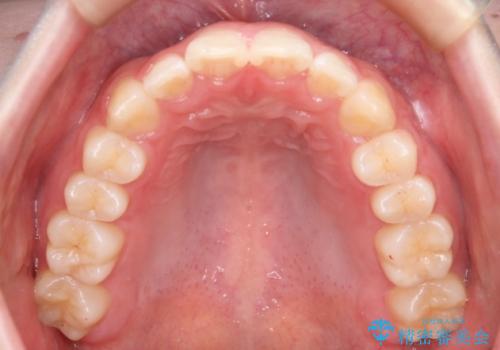

- 前歯のガタつきの改善を主訴に来院された患者様です。

ガタつきによる上顎正中の空隙や歯の突出感も気にされていました。

費用を抑えたいとの事だったので歯の移動量なども考慮し、インビザライン・ライトパッケージでの治療を計画しました。